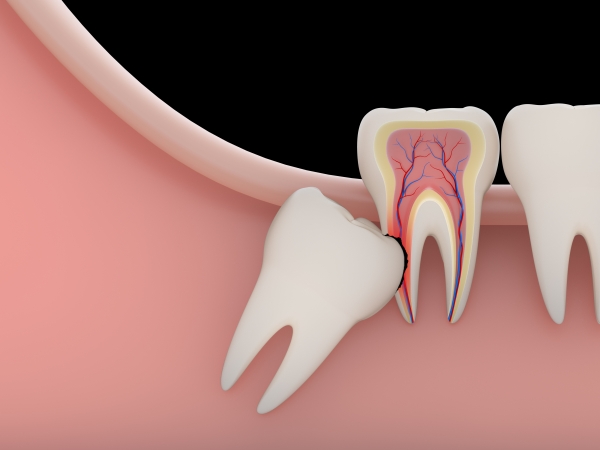

Không phải tất cả răng khôn đều cần nhổ. Nếu răng mọc thẳng, không gây đau nhức hay ảnh hưởng đến răng bên cạnh thì có thể giữ lại. Tuy nhiên, đa số răng khôn mọc lệch, mọc ngầm gây nhiều biến chứng.

Răng khôn mọc lệch, đâm vào răng số 7.

Sâu răng số 7.

Gây chen chúc, lệch lạc răng.